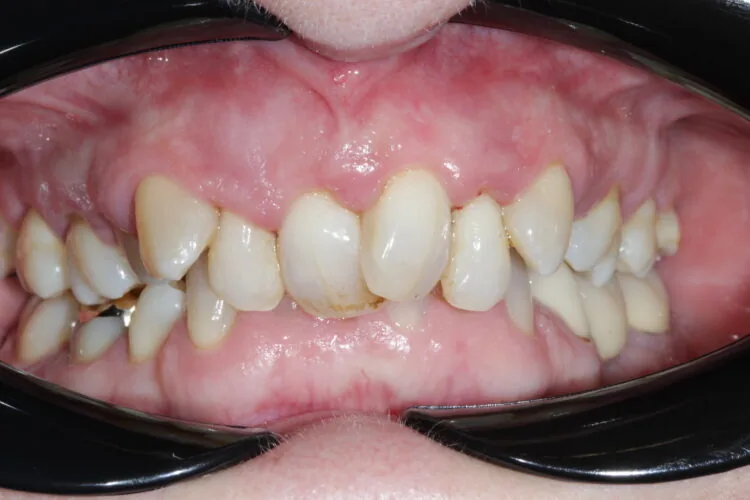

A woman in her mid-50s presented with the desire to improve her smile. She had not attended dental appointments for several years and felt ashamed of her teeth due to longstanding neglect. At the time of presentation, she had significant periodontal deterioration, particularly involving the upper four anterior teeth, which exhibited bone loss and mobility. Although she initially requested orthodontic treatment, this was not viable due to the advanced periodontal condition

Presenting condition

A comprehensive periodontal examination revealed widespread pocketing and clinical signs of mobility in the anterior region. The upper central and lateral incisors were the most severely affected, and they showed persistent instability despite improvements elsewhere. Generalised recession and attachment loss were confirmed, with periodontal charting from September 2023 and follow-up data in November 2023 demonstrating the extent of disease and its subsequent management.

Pre-treatment images